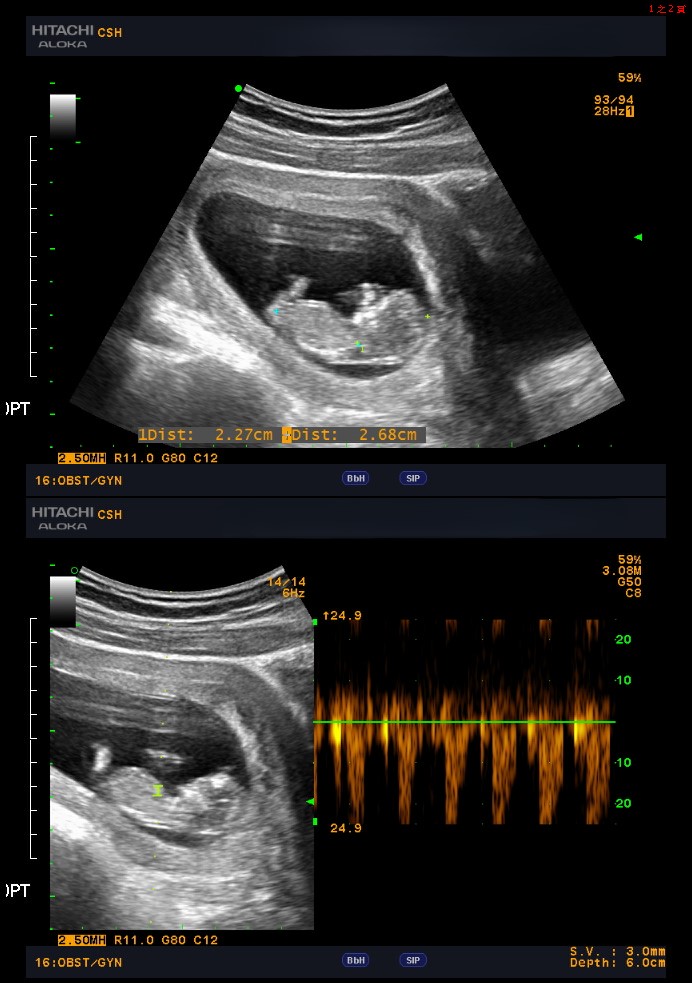

隨著時間推移,她的努力終於得到回報。 在經歷了長時間不孕的痛苦和焦慮後,她終於迎來了屬於她和丈夫的寶寶。

小美決定尋求幫助, 於是來到了我們的中山醫學大學附設醫院生殖醫學中心。經過詳細的檢查,我們發現了小美子宮內膜息肉以及維生素D缺乏, 這些是影響她懷孕的關鍵因素。